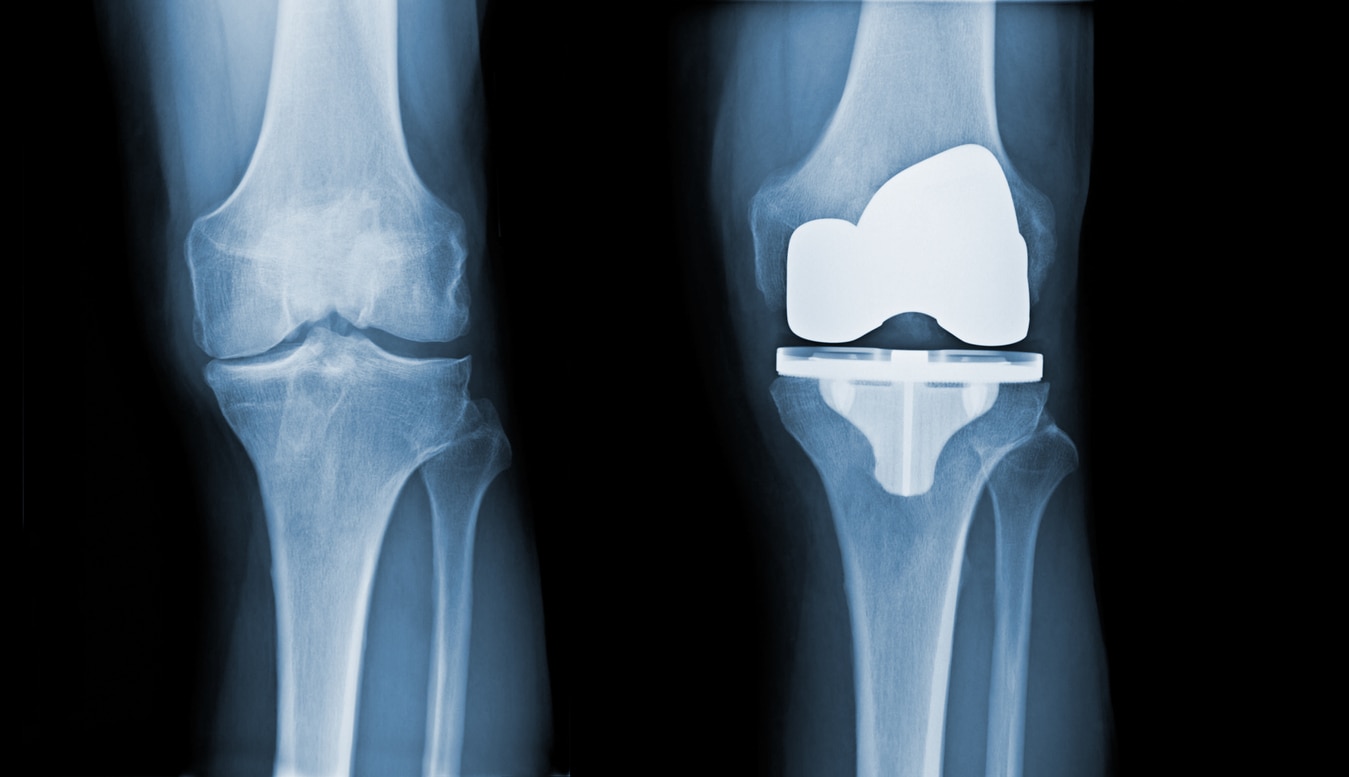

Total Knee Replacement

Total Knee Replacement by Dr. Ritesh Dang Senior Orthopedic Surgeon | 23+ Years of Experience | Rohini & Model Town, Delhi Are you struggling with constant knee pain, stiffness, or difficulty walking? When knee arthritis or injury severely impacts your mobility and quality of life, a Total Knee Replacement (TKR) can provide lasting relief and restore function. Dr. Ritesh Dang, a leading Orthopedic Surgeon in Delhi, specializes in advanced knee replacement surgery using modern, minimally invasive techniques designed for faster recovery and long-term results. 🔹 What is Total Knee Replacement? Total Knee Replacement is a surgical procedure where the damaged cartilage and bone of the knee joint are removed and replaced with a metal and plastic implant that mimics the natural movement of the knee. TKR is recommended when: 🦴 Knee pain persists despite medication or physiotherapy 🛌 Pain interferes with sleep or daily activities 🚶 Walking, climbing stairs, or even standing becomes difficult 🔄 Knee deformities (bow-legged or knock-kneed) worsen 🔹 Why Choose Dr. Ritesh Dang for Knee Replacement? With over 23 years of clinical and surgical expertise, Dr. Dang is known for delivering safe, effective, and patient-centered knee replacements. His approach includes: ✅ Minimally invasive surgical techniques for smaller incisions and quicker healing ✅ Use of advanced implants with proven longevity and durability ✅ Custom treatment plans based on your age, lifestyle, and health goals ✅ Comprehensive pre- and post-op care, including physiotherapy support ✅ High success rate and hundreds of satisfied patients across Delhi 🔹 Conditions Treated with TKR: Osteoarthritis – Age-related cartilage degeneration Rheumatoid Arthritis – Autoimmune joint inflammation Post-Traumatic Arthritis – After fractures or injuries Knee Deformities or misalignment Failed previous knee surgeries 🔹 Benefits of Total Knee Replacement: 🌟 Significant pain relief 🌟 Restored mobility and stability 🌟 Improved joint alignment and strength 🌟 Better sleep, mood, and independence 🌟 Return to low-impact activities like walking, swimming, or cycling 🔹 Consultation & Surgery Locations: 🏥 Yatharth Super Speciality Hospital 📍 4C, Institutional Area, North Extension, Model Town, New Delhi – 110033 🏥 Anand Ortho Care Centre 📍 B-39, Prashant Vihar Rd, Opp. CRPF School, Sector 14, Rohini, Delhi – 110085 🔹 Book Your Appointment Today: 🌐 Website: www.jointspecialistdelhi.com 📞 Phone: 08048035351 📧 Email: appointment@jointspecialistdelhi.com 👨‍⚕️ About Dr. Ritesh Dang: 23+ years of experience in orthopedic and joint replacement surgeries Specialist in Knee, Hip, and Shoulder Replacements Member – Delhi Medical Association (DMA) Trusted by patients for ethical care, surgical precision, and compassionate follow-up